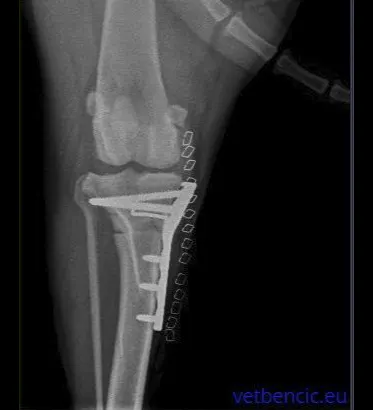

Ova operacija uključuje pravljenje polukružnog reza na vrhu tibije i rotiranje platoa tibije dok prethodni nagib kosti više ne nestane. Kost se naknadno fiksira odgovarajućom pločicom i vijcima.

Ova operacija uključuje iste principe kao i TPLO, s rezom na tibiji kako bi se omogućila promjena geometrije. Osnovno načelo je da promijenjeni smjer istezanja skupine mišića kvadricepsa proizvodi sile preko zgloba koljena koje neutraliziraju tendenciju bedrene kosti da klizi niz kosinu tibijalnog platoa. I TTA i TPLO imaju za cilj napraviti kut između tibijalnog platoa i patelarne tetive pod pravim kutom, čime se suprotstavlja tendenciji bedrene kosti da klizi niz kosinu tibijalnog platoa. Budući da kost zacjeljuje učinkovitije od ligamenata, ove metode pružaju mnogo veću čvrstoću od metoda popravka ligamenata. Oporavak je puno bolji, psi već 1-3 dana nakon operacije hodaju na bolesnoj nozi. Brz povratak normalnim aktivnostima vrlo je važan za teške pse, atletske pse, pse s blagom hromošću i za pacijente koji imaju bilateralne rupture. Kod takvih se TPLO može izvesti na oba koljena istovremeno. Koja je metoda prikladnija ovisi o individualnim anatomskim karakteristikama životinje. U većini slučajeva obje su metode primjerene.